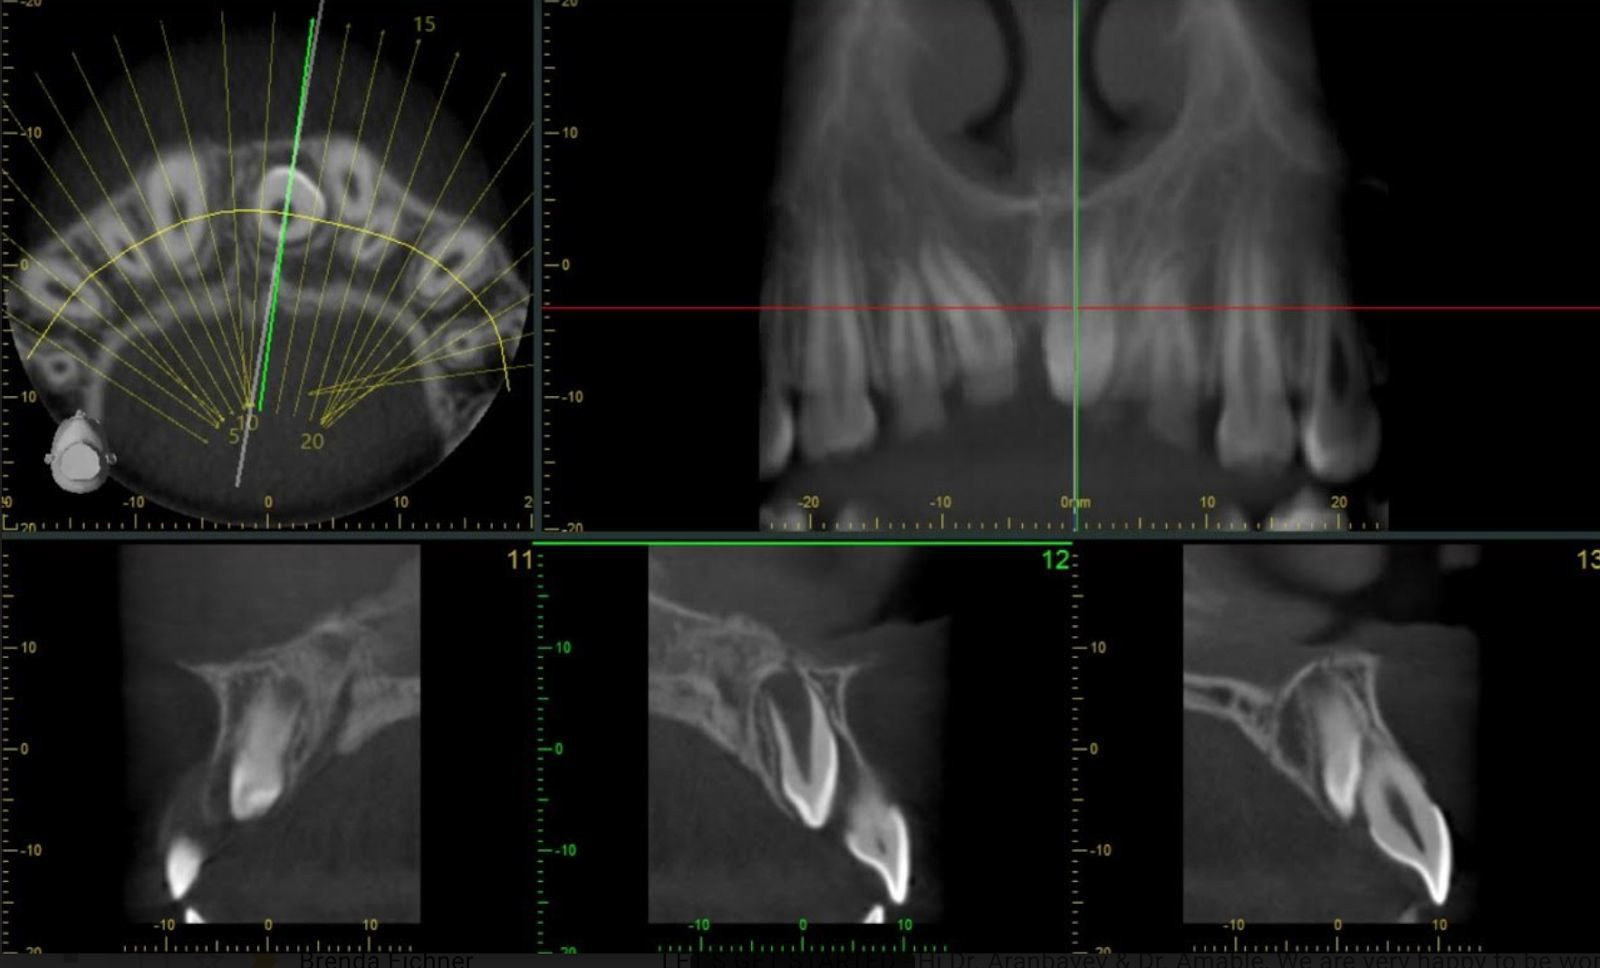

- CT-Scan was ordered and taken for evaluation of exact position/location of mesiodens.

- Extraction of Mesiodens under nitrous oxide and local anesthesia. Oral surgeon resident performed the mesiodens removal without any complications.

Figures 22-24: CT scan of Mesiodens, and post operative diagnostic casts